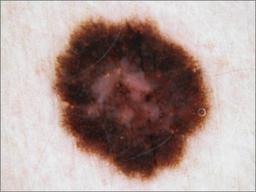

{

"age_approx": 60,

"anatom_site_general": "upper extremity",

"concomitant_biopsy": true,

"diagnosis_1": "Malignant",

"diagnosis_2": "Malignant melanocytic proliferations (Melanoma)",

"diagnosis_3": "Melanoma, NOS",

"diagnosis_confirm_type": "histopathology",

"image_type": "dermoscopic",

"melanocytic": true,

"sex": "female"

}